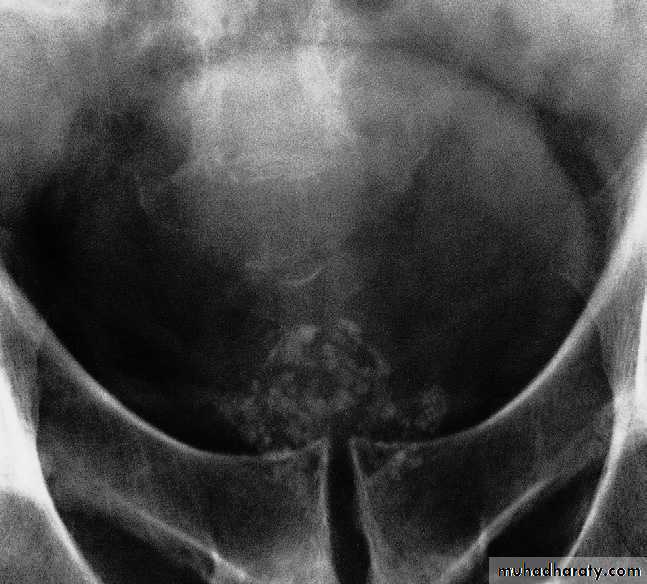

Prostatic calcification

Prostatic calcification is due to numerous prostatic calculi.It is so common that it can be regarded as a normal finding in older men, and shows no correlation with the symptoms of prostatic hypertrophy nor any relation to prostatic carcinoma. Flecks of calcification of varying size, approximately symmetrical about the midline, are seen just inferior to the bladder.Bladder outflow obstruction: causes of obstruction